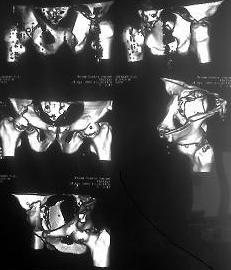

Re: Перелом вертлужных впадин

послал Миронов Андрей 26 Апрель 2008, 22:41

Извините, пробую еще раз